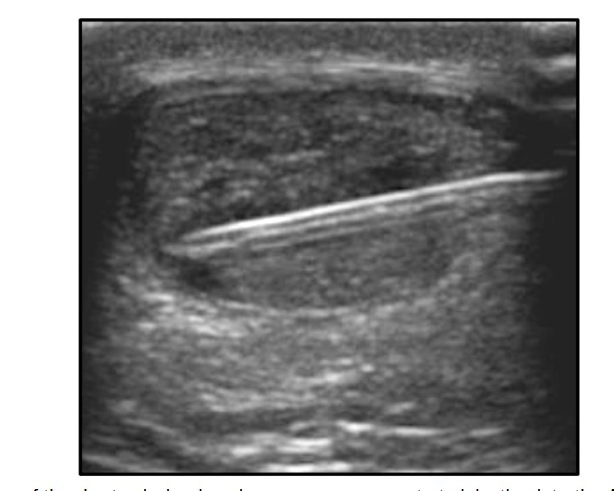

Post-procedural care included limited partial weight bearing in a full-length boot day and night for two weeks after the percutaneous ultrasonic tenotomy, then full weight bearing in the boot for the next 2-3 weeks until follow-up. Heat was utilized for post-procedural pain control as well as oral oxycodone only for the two days following the bone marrow concentrate and acetaminophen. Non-steroidal anti-inflammatory drugs were avoided for two weeks before and two weeks after the bone marrow concentrate procedure. Physical therapy began one week after the bone marrow concentrate, beginning with range of motion and isometric exercises, progressing to concentric calf strengthening between 2-4 weeks post-procedure. By 6 weeks, eccentric calf strengthening began and progressed until 3 months post-procedure. By three months post-procedure, he was completely pain-free and had returned to long and fast walking on even surfaces but had not returned to hiking. At his six-month follow-up he remained 100% pain-free and achieved a full functional recovery, including jumping sports and day hikes of 20 miles with over 5,000 feet of elevation gain. At his one and two-year follow-up examinations, he remained pain-free and functioned at his prior level. Interestingly, there was still focal swelling and tenderness at both the three and six-month follow-up examinations, both of which had resolved by one year. Repeat MRI at seven months showed complete healing of previous Achilles tendon interstitial tear, as shown in Figure 3.

Figure 3: Fat suppressed T2-weighted magnetic resonance image of the distal leg revealing complete resolution of the hyperintense lesion in the midportion Achilles tendon shown in the pre-treatment MRI. (A) is the axial view and (B) is the sagittal view.